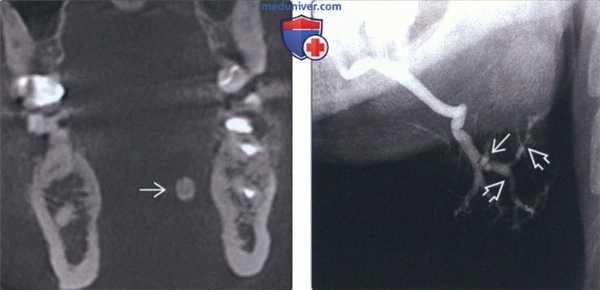

(Слева) На корональной КЛКТ определяется поднижнечелюстной сиалолит в левом вартоновом протоке. Обратите внимание, что сиалолит образован слоями с обызвествлением различной степени выраженности и имеет овоидную форму.

(Справа) На традиционной сиалограмме определяются рентгеноконтрастный и рентгенопрозрачный в сиалолиты. Наблюдается классическая картина («связка сосисок») вторичного сиалодохита с расширением протока и стриктурами. 20% поднижнечелюстных сиалолитов недостаточно обызвествлены и выглядят как дефекты наполнения (рентгенопрозрачные включения).